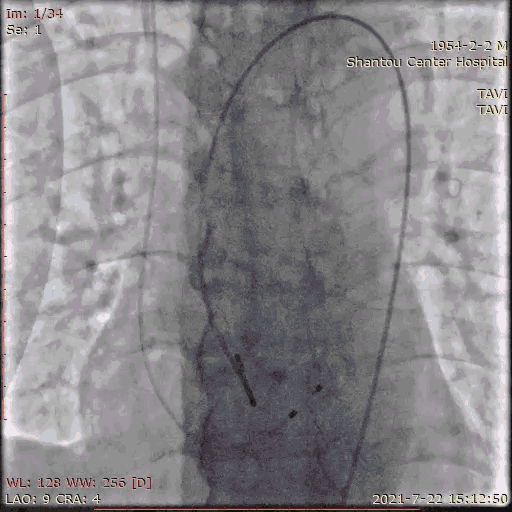

主动脉根部造影

临时起搏器植入后,辅入路穿刺,猪尾导管置于无冠窦底进行主动脉根部造影。

初步判断释放体位是否合适。

观察瓣叶活动度、是否合并反流,有利于跨瓣。

左右冠通畅,存在一定反流,有一定耐受能力,球扩时,循环崩溃风险较小。

左冠窦瓣叶活动度高、无钙化,无冠窦右冠窦活动度减轻,且钙化集中在基底部,右冠风险较左冠低。

手术流程

术前怀疑冠脉有狭窄,一站式冠脉造影检查,狭窄程度无需行PCI。

冠脉造影

左右冠通畅,存在一定反流,有一定耐受能力,球扩时,循环崩溃风险较小。双侧瓣叶活动度高。